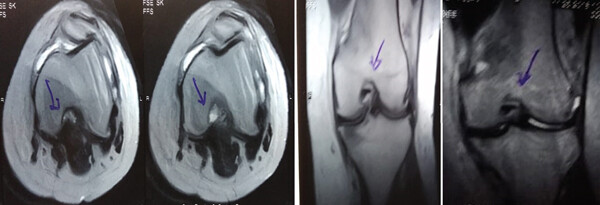

MRI:治療前后的MRI結果

治療前 MRI 顯示內側和外側半月板后角 III 級撕裂。

治療后MRI檢查顯示內側和外側半月板后角撕裂有所改善。患者癥狀改善,日常生活活動能力增強。

結論:間充質干細胞治療后,MRI檢查顯示內側和外側半月板后角撕裂有所改善 ,關節功能也有改善,未出現嚴重不良事件。可以達到干細胞治療半月板損傷短期療效的目標。